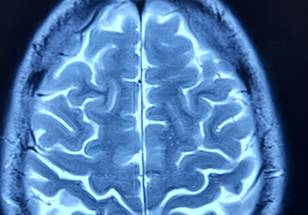

In a study published today in eClinicalMedicine, Dr. Newcombe and colleagues show that an advanced form of MRI known as diffusion tensor imaging (DTI) can substantially improve existing prognostic models for patients with concussion who have been given a normal CT brain.

DTI measures how water molecules move in tissue, providing detailed images of the pathways, known as white matter tracts, that connect different parts of the brain. Standard MRI scanners can be adapted to measure this data, which can be used to calculate a DTI "score" based on the number of different brain regions with abnormalities.